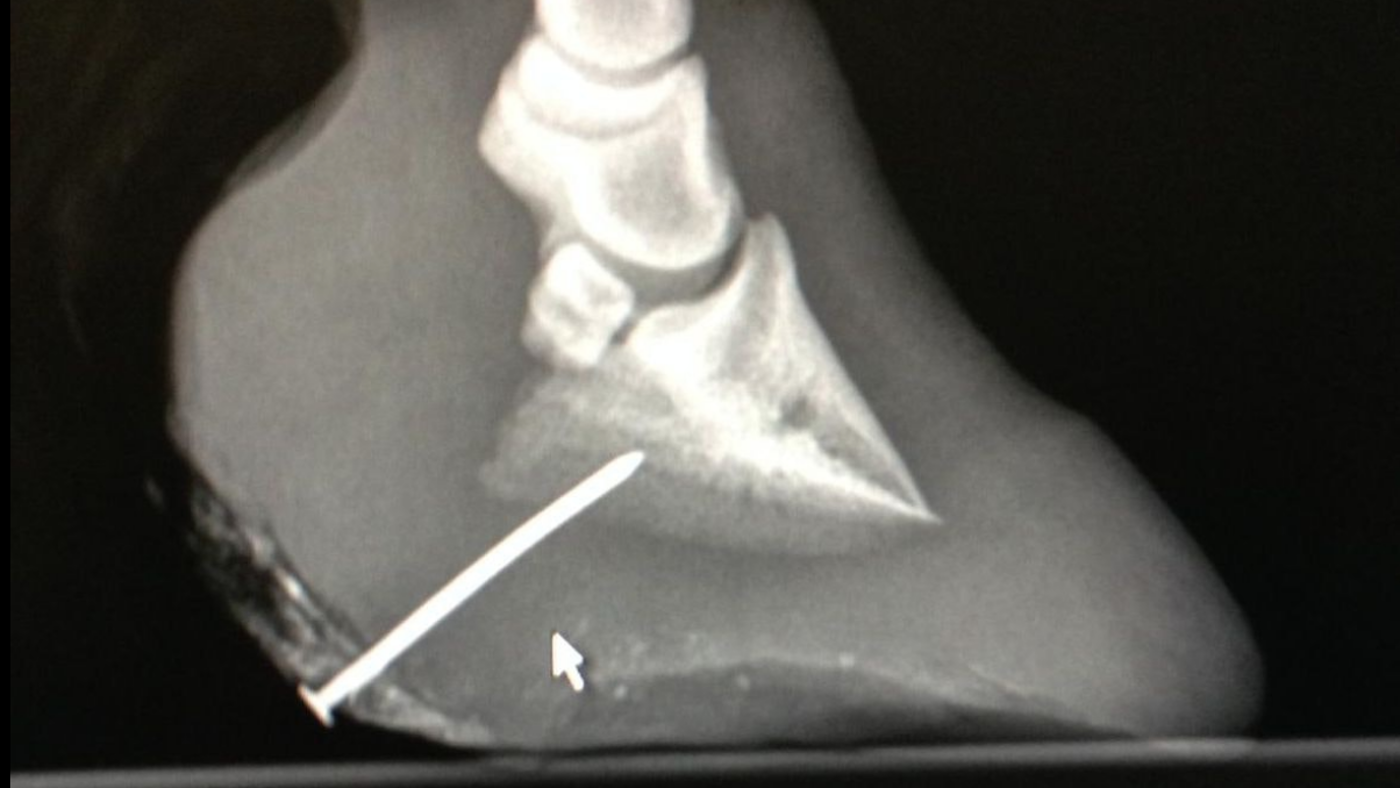

“An X-ray of his hooves revealed he also had a one and a quarter-inch nail sticking into his foot, that had clearly been there for some time. The nail and dressings have now been removed and he has been given anti-tetanus treatment and antibiotics.”